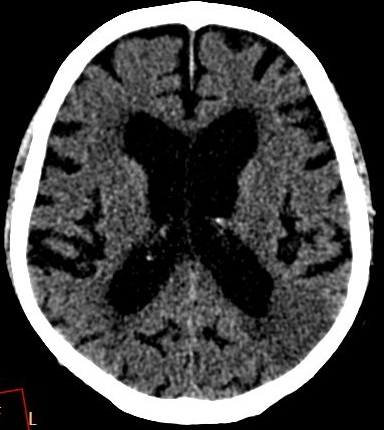

10.1.2.3. Computed Tomography (CT):_

It is an excellent and a widely available method for imaging the central nervous system.

It reliably depicts bony structures, calcifications and cerebrospinal fluid.

It is also capable to distinguish white matter from grey matter, as well as the CSF (0 HU) based on their density differences.

Fresh hemorrhage on CT appears hyperdense, therefore hemorrhagic stroke and subarachnoid bleeding can be promptly diagnosed with CT examinations.

CT:The primary goal of the diagnostics is to rule out hemorrhage, for which CT is very sensitive. It is essential to differentiate ischemic stroke from hemorrhagic stroke because their therapeutic approaches and consequences are fundamentally different. When bleeding is excluded, based on the neurologic assessment of the patient (deficit, age of stroke etc.) thrombolytic therapy can be initiated by the neurologist either as a generalized (intravenous) or a local procedure (selective thrombolysis – perormed by a radiologist -).

In acute phase (12-24 hours after the occlusion of the middle cerebral artery) on CT hypodense basal ganglia, the loss of cortical white-grey matter differentiation and sulcal effacement are the characteristic imaging findings.

On CT images acute bleeding always presents as hyperdensity. (One has to keep it mind that hyperdensity of the blood is affected by the hematocrit levels, hence making the diagnosis more difficult.) Intraparenchymal blood is dominated by a destructive appearance (mass-effect) and it is surrounded by hypodensity as a sign of perifocal edema. It often breaks into the ventricles. In patients lying in a supine position they collect (sediment) at the occipital horn of the lateral ventricles, creating a hyperdense liquid-to-liquid levels. Later on, the density of blood decreases and shows a peripheral ring or rim-like contrast enhancement without mass-effect.